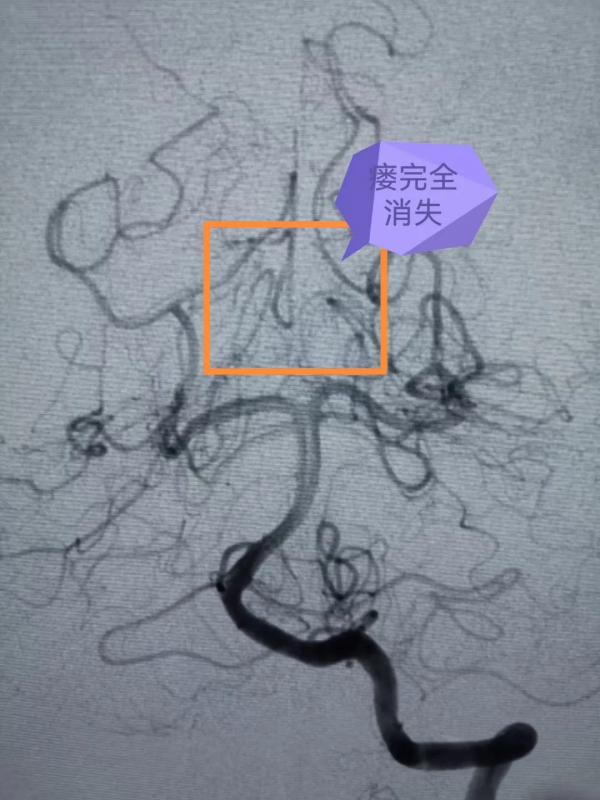

但是腦血管疾病種類較多,形態多樣,頭顱MR仍然無法進一步確診,診斷腦血管疾病的“金標準”則是全腦血管造影(DSA),海西州人民醫院此前已經具備了此項特殊檢查的硬體設施和人員配備。巴特爾副主任醫師更是在2年前就在浙大一院進修學習掌握了全腦血管造影技術。於是,他隨後即帶領海西州人民醫院的本土團隊為大梅順利開展了全腦血管造影術,術中發現大梅的小腦幕區貼近腦幹處,有個直徑約1cm、像蚯蚓一樣扭曲的腦血管畸形。

專家團隊在大梅的大腿根部股動脈穿入筆芯粗細的導管,然後在腦血管造影機的X線引導下,將一米多長的細若髮絲的微導管透過血管小心翼翼送至腦血管畸形部位,由於血管畸形位於腦深部,供血動脈迂曲細長,角度刁鑽,手術困難極大,但是專家團隊小心仔細,鍥而不捨,經過5個多小時的緊張手術,最終將腦血管畸形完全栓塞。手術後,大梅的腦部畸形團塊消失,恢復良好。